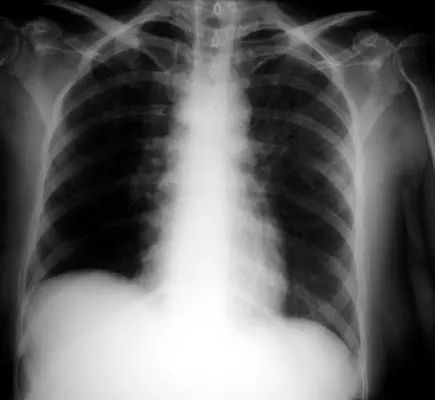

图1.1 细菌性肺炎。右上叶肺炎患者的放射影像。胸廓前后径增大,提示有慢性阻塞性肺疾病(COPD)。